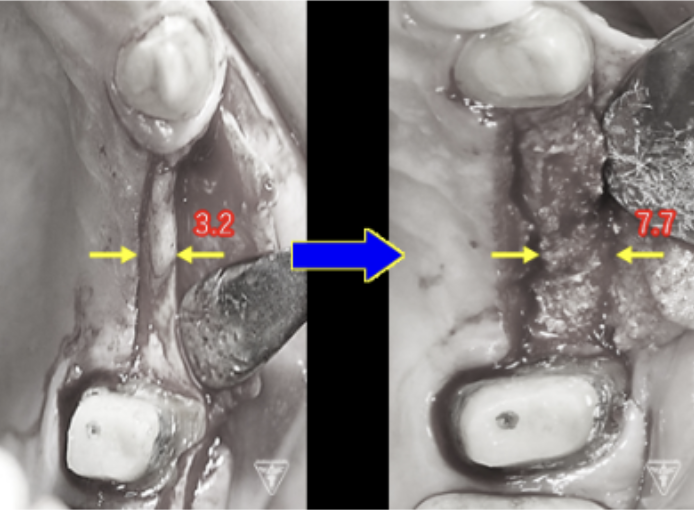

骨再生治療